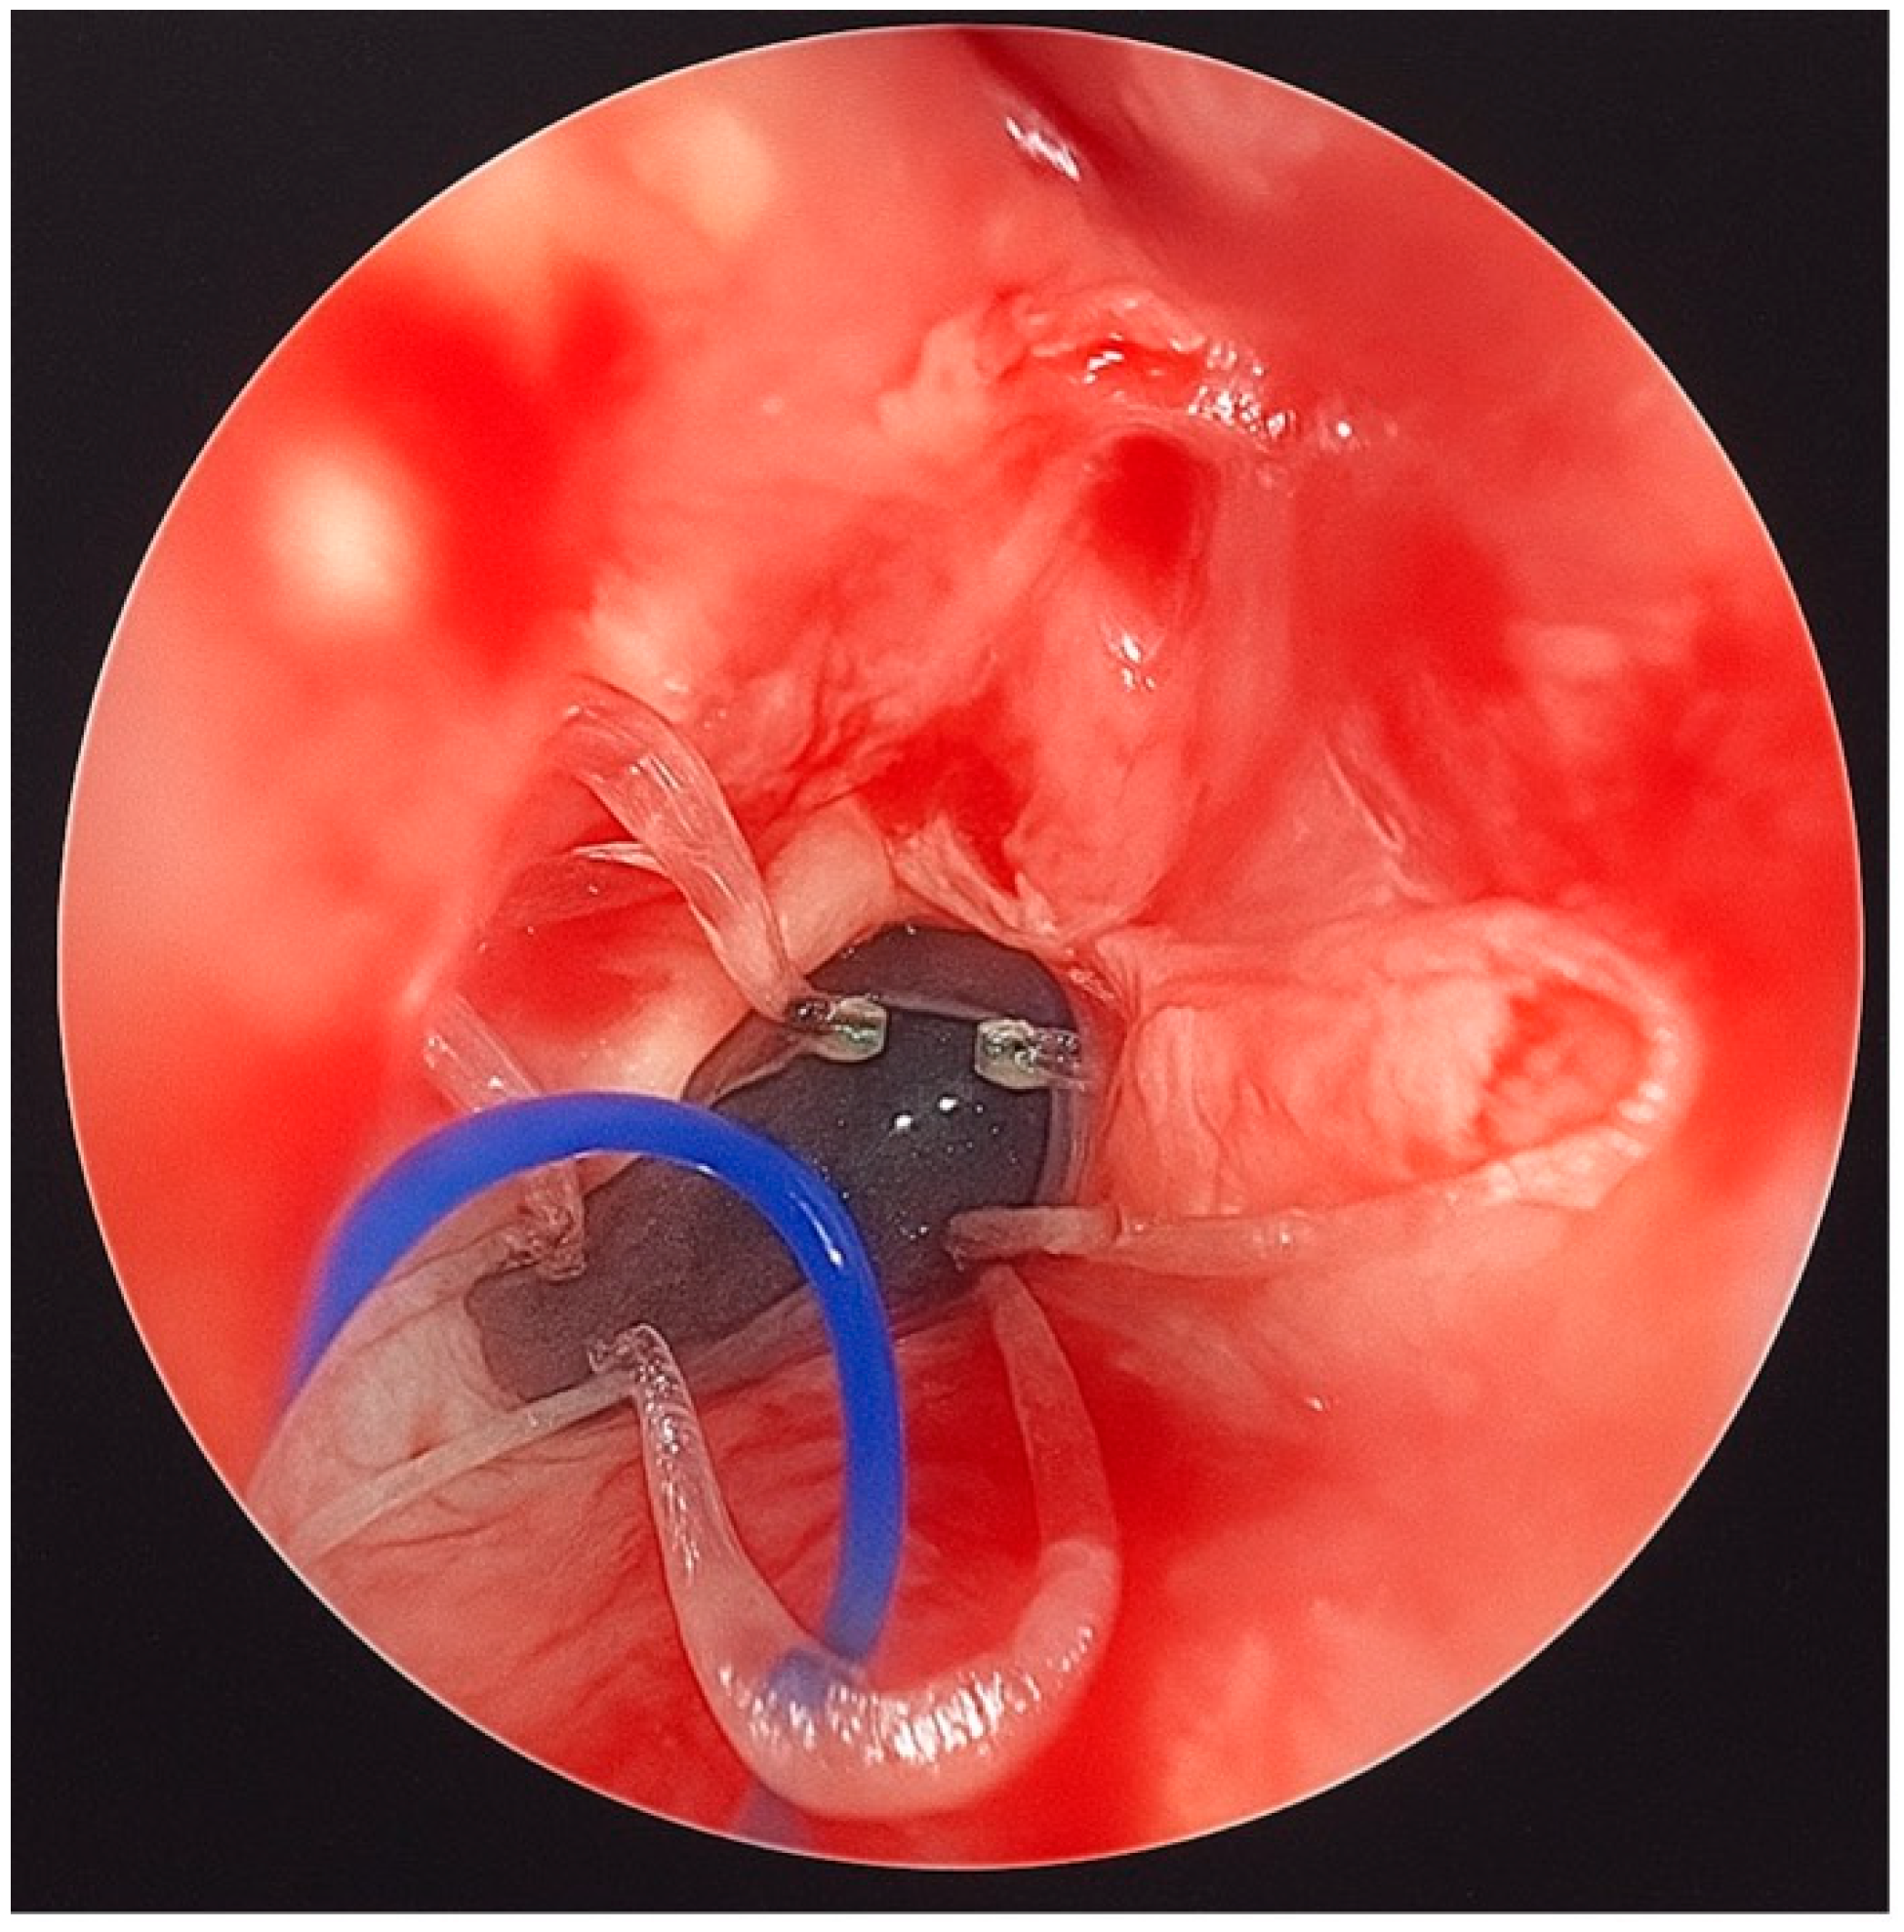

Finally, a steroid-eluting, bioabsorbable nasal stent (PROPEL Contour type) was tailored to fit the neochoana and placed in position (Figure 2 and Figure 3). The use of a steroid-eluting, bioabsorbable stent was chosen to maintain patency of the neochoana and reduce the risk of restenosis, as supported by previous studies in older children. As this type of stent is originally designed for placement within the frontal recess, a dedicated applicator is usually provided. However, this applicator could not be used to position the stent at the choanal level.

An ear suction cannula was then inserted into the Nelaton tube to allow the surgeon to push the stent forward during deployment (Figure 2). The Nelaton tube containing the stent was advanced to the level of the choanae, while a second operator carefully pushed the suction cannula forward and simultaneously withdrew the Nelaton tube, releasing the stent precisely in position (Figure 3). The external prolene suture was secured to the skin using adhesive tape, similar to the fixation of a nasogastric tube, to prevent displacement.

Figure 3. The PROPEL Contour stent was placed in the patient’s neochoana.